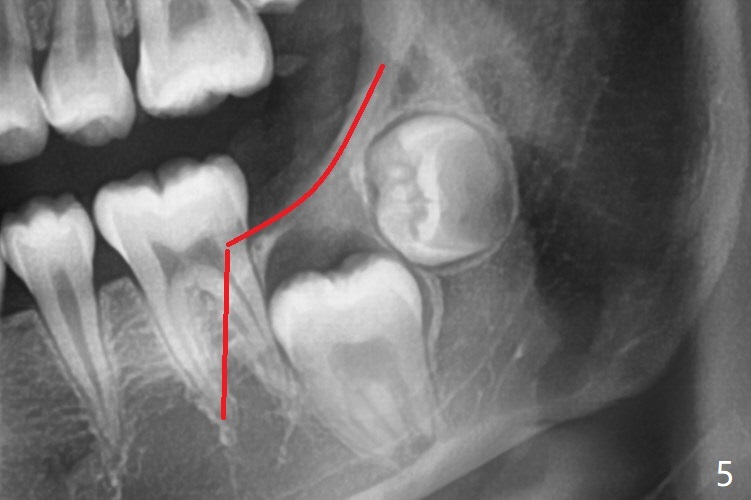

Treatment planning of surgical access to the impacted 7 (Fig.1) before CT analysis (to be canceled due to finance) include extraction of 8 (Fig.2) and removal of the bone coronal to 8 (Fig.3 red) so that there will be no bony block to 7 eruption (Fig.4). Place PRF or collagen plug in 8 socket to facilitate healing (Fig.3). Attach a retraction chain to the occlusal or buccal surface of 7 (Fig.6 pink) whenever it is convenient in term of hemorrhage and access (as mesial as possible). Remove 16 niti wires for brushing when the patient arrives. Cut 18 ss wire longer in the LL end (Fig.6 green to be bent to hook power chain (yellow)). Incision is shown as red in Fig.5. After 3 month delay, the thick buccal plate is removed from LL8 (1st) and 7 (2nd in sequence, as compared to Fig.2) to expose these unerupted teeth. In fact CT is not taken to decrease budget on the divorcing parents. A retraction chain is placed before extraction of LL8 with an intention to reduce hemorrhage (Fig.7). Although extraction requires several sectioning of the tooth, hemorrhage is mild to moderate. Instead of PRF and sticky bone (as compared to Fig.3), Osteogen plug is placed in the socket (Fig.8 OP). The bony septum between the 2 sockets is intentionally kept in place (*). 事实的确这样发生(图九:*)。埋伏牙不仅上移(^),而且远中移动(>),因为牵引方向(红虚线(橡皮筋),挂在上牙弓丝(图九:20ss:图十:18ss(之前))远端勾,积极牵引三个星期)。下次左上7放置舌侧纽扣,让病人更换橡皮筋。其实纽扣粘不住,上牙弓丝远中勾也不现实,只能使用橡皮筋挂在左上6,经常断。术后6个月,左下7继续上移(图十一)。这种低效率牵引仍然有效,牙齿继续上移,牙根长长(图十二:空箭头),但是受到左下6远中阻挡(*),所以下次在左上7咬合面装置舌侧纽扣和closed spring,改善牵拉方向(红箭头)。